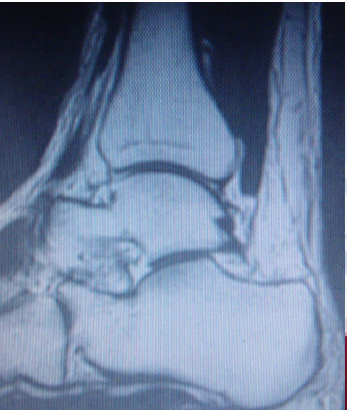

带线锚钉在中踝外科的应用

1.带线锚钉单纯下胫腓联合分离

下胫腓联合由下胫腓前韧带、后韧带、下横韧带及最坚固的骨间韧带紧密连结构成。下胫腓联合分离是由于踝关节受强力外翻外旋暴力所致,可单独发生,但多合并踝关节其他韧带损伤或骨折、脱位。如治疗不及时或处理不恰当,常遗留慢性疼痛、关节不稳及创伤性关节炎,严重影响踝关节功能。

传统法:下胫腓联合分离手术固定方法很多,有螺钉、生物可吸收植入物、腓骨钩、线扣固定等。

带线锚钉法:

①创伤小,在外踝上方作2 cm小切口,不用二次取出。早期负重,出现断钉情况很少;

②编织线的弹性模量与螺钉、可吸收螺钉相比更接近韧带;

③编织线与骨间韧带方向相一致,类似于韧带的力学重建。同时在腓骨上编织线的走行与腓骨纵轴一致,这样即使编织线对腓骨有切割也不容易引起腓骨的骨折。